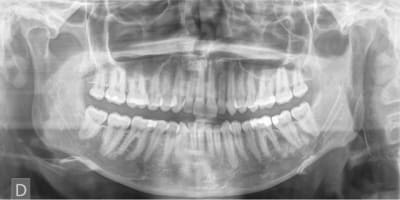

Pouvez-vous m'éclairer sur la nature de l'image radio-opaque visible au niveau des apex de 36 et 37?

Patiente 27 ans, bonne santé générale.

S'est plaint de douleurs et d'une tuméfaction au niveau de la mâchoire inf côté gauche pendant 15 jours.

Tuméfaction toujours présente mais non douloureuse.

Vitalité des dents secteur 3 +, percussion + (patiente sensible)

Malgré ton test vitalité positif (vitalité certainement partielle), tu vas sans doute devoir utiliser tes cones de gutta pour 35 et 36!

essaye de préciser la nature des radios opacités du secteur (lithiases ? )

et pense à une fracture /fêlure

peut être un cémentoblastome.